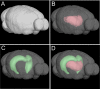

The mechanisms underlying the selective targeting of specific brain regions by different neurodegenerative diseases is one of the most intriguing mysteries in medicine. For example, it is known that Alzheimer's disease primarily affects parts of the brain that play a role in memory, whereas Parkinson's disease predominantly affects parts of the brain that are involved in body movement. However, the reasons that other brain regions remain unaffected in these diseases are unknown. A better understanding of the phenomenon of selective vulnerability is required for the development of targeted therapeutic approaches that specifically protect affected neurons, thereby altering the disease course and preventing its progression. Prion diseases are a fascinating group of neurodegenerative diseases because they exhibit a wide phenotypic spectrum caused by different sequence perturbations in a single protein. The possible ways that mutations affecting this protein can cause several distinct neurodegenerative diseases are explored in this Review to highlight the complexity underlying selective vulnerability. The premise of this article is that selective vulnerability is determined by the interaction of specific protein conformers and region-specific microenvironments harboring unique combinations of subcellular components such as metals, chaperones and protein translation machinery. Given the abundance of potential contributory factors in the neurodegenerative process, a better understanding of how these factors interact will provide invaluable insight into disease mechanisms to guide therapeutic discovery.